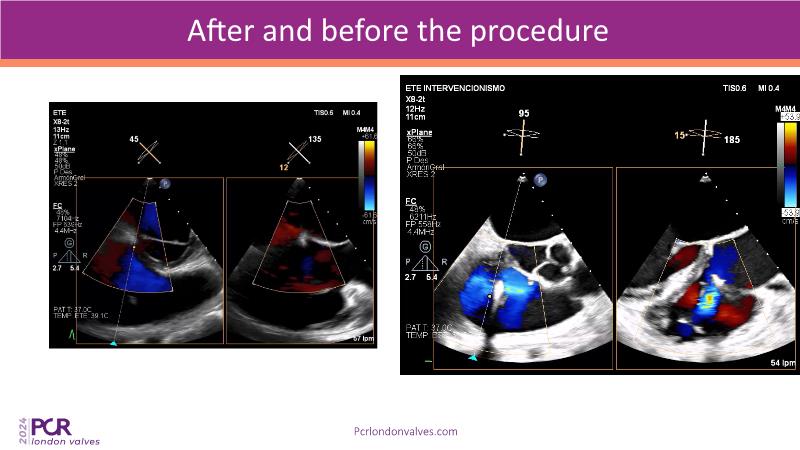

This session examines two compelling cases: a 78-year-old woman with paroxysmal atrial fibrillation, chest trauma, an osteoporotic sternum fracture, and NYHA II exertional dyspnoea, and an 82-year-old man with chronic three-vessel coronary artery disease, bradycardic AF, peripheral arterial disease, spinal stenosis, and chronic kidney disease. Through their study, discover the intricate anatomy of atrioventricular valves, the therapeutic challenges they pose, and the growing significance of transcatheter edge-to-edge repair (TEER) therapies. The discussion also highlights the value of multidisciplinary strategies in managing complex valve diseases effectively.